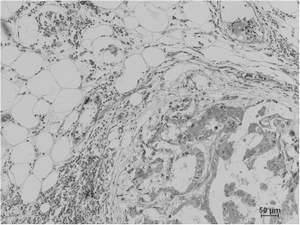

Immunohistochemical analysis of paraffin-embedded Human Breast Carcinoma using Pan Methylated Lysine Monoclonal Antibody.